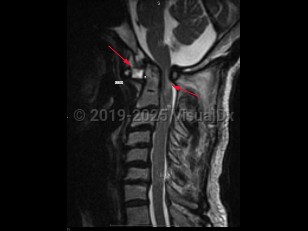

Atlantoaxial instability

Atlantoaxial instability (AAI) is defined as excessive motion between the first cervical vertebra, the atlas, and the second cervical vertebra, the axis. The atlantoaxial segment is an anatomically complex section of the spinal column, composed of unique bones, articulations, and ligaments, with critical neurovascular structures intimately involved. The atlantoaxial segment is responsible for significant motion in the spine, and, in fact, is responsible for over half the possible axial rotation of the cervical spine. Disruptions of any of the ligaments or articular processes that afford nonpathologic motion of the atlantoaxial segment may result in instability of the complex. AAI can occur due to trauma, rheumatoid arthritis, congenital abnormalities (including up to 20% of Down syndrome patients), degenerative changes, head and neck infections, neoplasms, or iatrogenic etiologies. Most commonly, AAI results from compromise of the ligamentous complex; however, fractures or destructive processes affecting the osseous elements may also result in AAI.

AAI can occur in 3 directions: rotation, flexion-extension, and distraction leading to excessive displacement, which can result in subluxation or even dislocation.

Anterior atlantoaxial subluxations are more common in adults and result from any of the pathologies listed above. Anterior subluxations result in neurologic deficits or death in one-third of patients. Patients with rheumatoid arthritis (RA) are at most risk for dislocation in the anteroposterior (AP) plane but can develop rotational AAI as well.